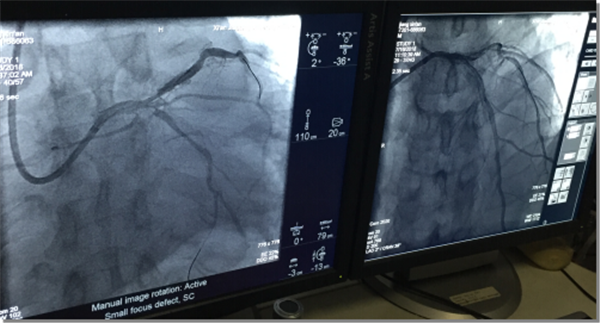

60岁的蒋先生因阵发性心慌1年余入院。入院检查提示三支病变,左前降支近中段呈80-95%狭窄,前降支狭窄最重处最小管腔面积为2.7平方毫米,管腔钙化360°,有行冠状动脉旋磨术指征。在家属知情同意下,7月16日上午,在干二病区科高洁主治医师、成海娟住院医师、井兰兰护士的陪同与协助下,心内科邓捷副主任医师、朱参战副主任医师、王新宏主治医师等人为蒋先生成功实施了冠状动脉旋磨术,并于前降支、左主干、回旋支各植入1枚支架。术后患者未诉不适,继续药物治疗,随访良好。

术前术后造影情况对比